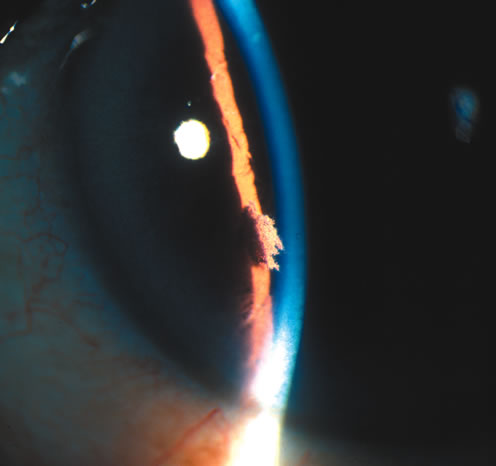

Slit-lamp examination reveals iris stromal fibers and blood vessels that remain attached to one portion of the iris with the loose ends floating freely in the anterior chamber, producing the so-called shredded-wheat appearance. The location of iridoschisis is often inferior (Fig. 3).

Fig. 3. Iridoschisis located inferiorly. Note the split stromal fibers floating in the anterior chamber. (© University of Illinois at Chicago.)